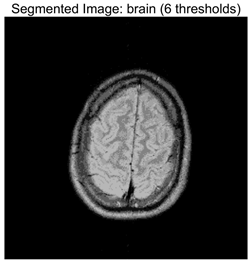

Table 8 presents the distributions of the optimal thresholds selected by each algorithm on the image histograms. Table 9 reports the mean and standard deviation of the best fitness values obtained by each algorithm based on the Otsu objective function, along with their average performance rankings. Furthermore, Table 10, Table 11 and Table 12 summarize the mean, standard deviation, and average ranking of each algorithm in terms of PSNR, FSIM, and SSIM, respectively. The experiments cover four threshold levels (4, 6, 8, and 10), with all results obtained through optimal threshold search using the Otsu criterion.

Table 9 focuses on the optimal fitness values obtained based on the Otsu objective function (maximization of inter-class variance), which directly reflects the algorithms’ ability to search for segmentation thresholds. Higher Ave values indicate that the thresholds are closer to the global optimum, while lower Std values reflect greater consistency across multiple runs. From the data distribution, RLTC-SCA exhibits a dual advantage of “high Ave + low Std” across all image and threshold-level combinations. For instance, in the brain image (a medical brain image with complex grayscale distribution), when TH = 4, RLTC-SCA achieves an Ave value of 3.7306 × 103, comparable to AGPSO and MVO, but its Std value (2.3126 × 10−12) is only 1.53 × 10−11 times that of AGWO (1.5156 × 10−1), showing virtually no fluctuation. At TH = 10, its Ave value (3.7694 × 103) still surpasses standard SCA (3.7644 × 103) and AGWO (3.7691 × 103), with a Std value (1.3312 × 10−1) amounting to merely 3.81% of IVYA (3.4907 × 100), demonstrating stable threshold-search accuracy even at high threshold levels. In the camera image (industrial scene image with low grayscale contrast), at TH = 4, RLTC-SCA’s Ave value (4.6008 × 103) is 0.01% higher than the second-best AGPSO (4.6003 × 103), while its Std value (0.69397) is only 39.44% of standard SCA (1.7594), validating that the reinforcement learning-based action selection strategy can dynamically adjust search actions to avoid threshold selection bias in smooth grayscale distributions. In contrast, algorithms such as IVYA, lacking guided global exploration, show lower Ave values and Std values exceeding 3.0 × 100 in most images, ranking last (8th) in the Friedman ranking, compared with RLTC-SCA ranked 1st.